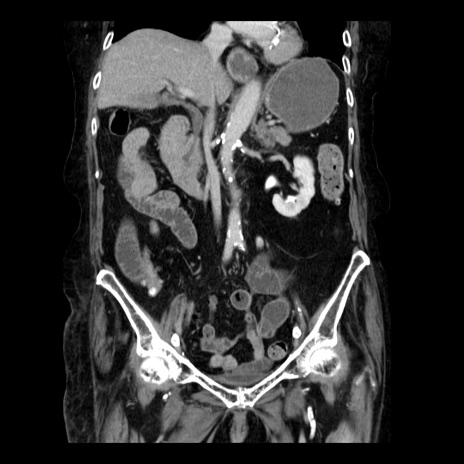

症例14(冠状断像)

【症例】 90歳代女性

【主訴】 腹痛・嘔吐

【現病歴】今朝から左側腹部痛を認めた。 経過観察していたが、嘔吐を認めたため来院。

【既往歴】 子宮癌術後

【身体所見】 意識清明、BP 127/54mmHg、P 98bpm Sp02 95%(RA)、BT 35.8°C、腹部平坦・軟腸ぜん動音聴取良好、右下腹部圧痛(+) 反跳痛なし

【データ】WBC 9800、CRP 0.46